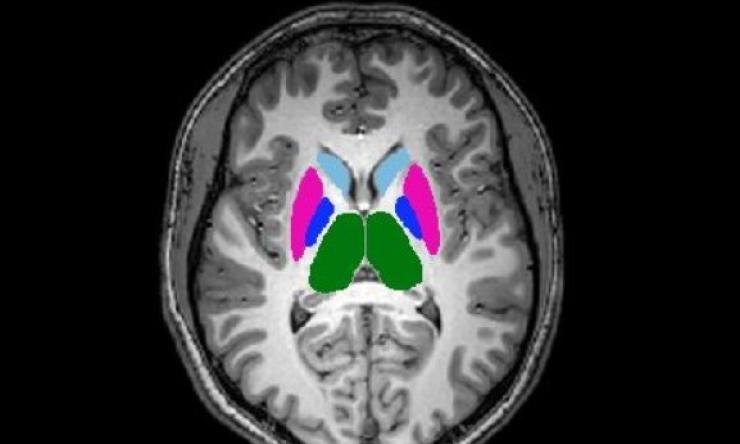

Our research addresses various aspects of psychiatric conditions. We are studying several ways the body and the brain affect each other, including how mental illness and its treatment may affect weight and development and bone health. We are also interested in studying how body iron affects brain development and functioning and the role of gut bacteria in mental health.